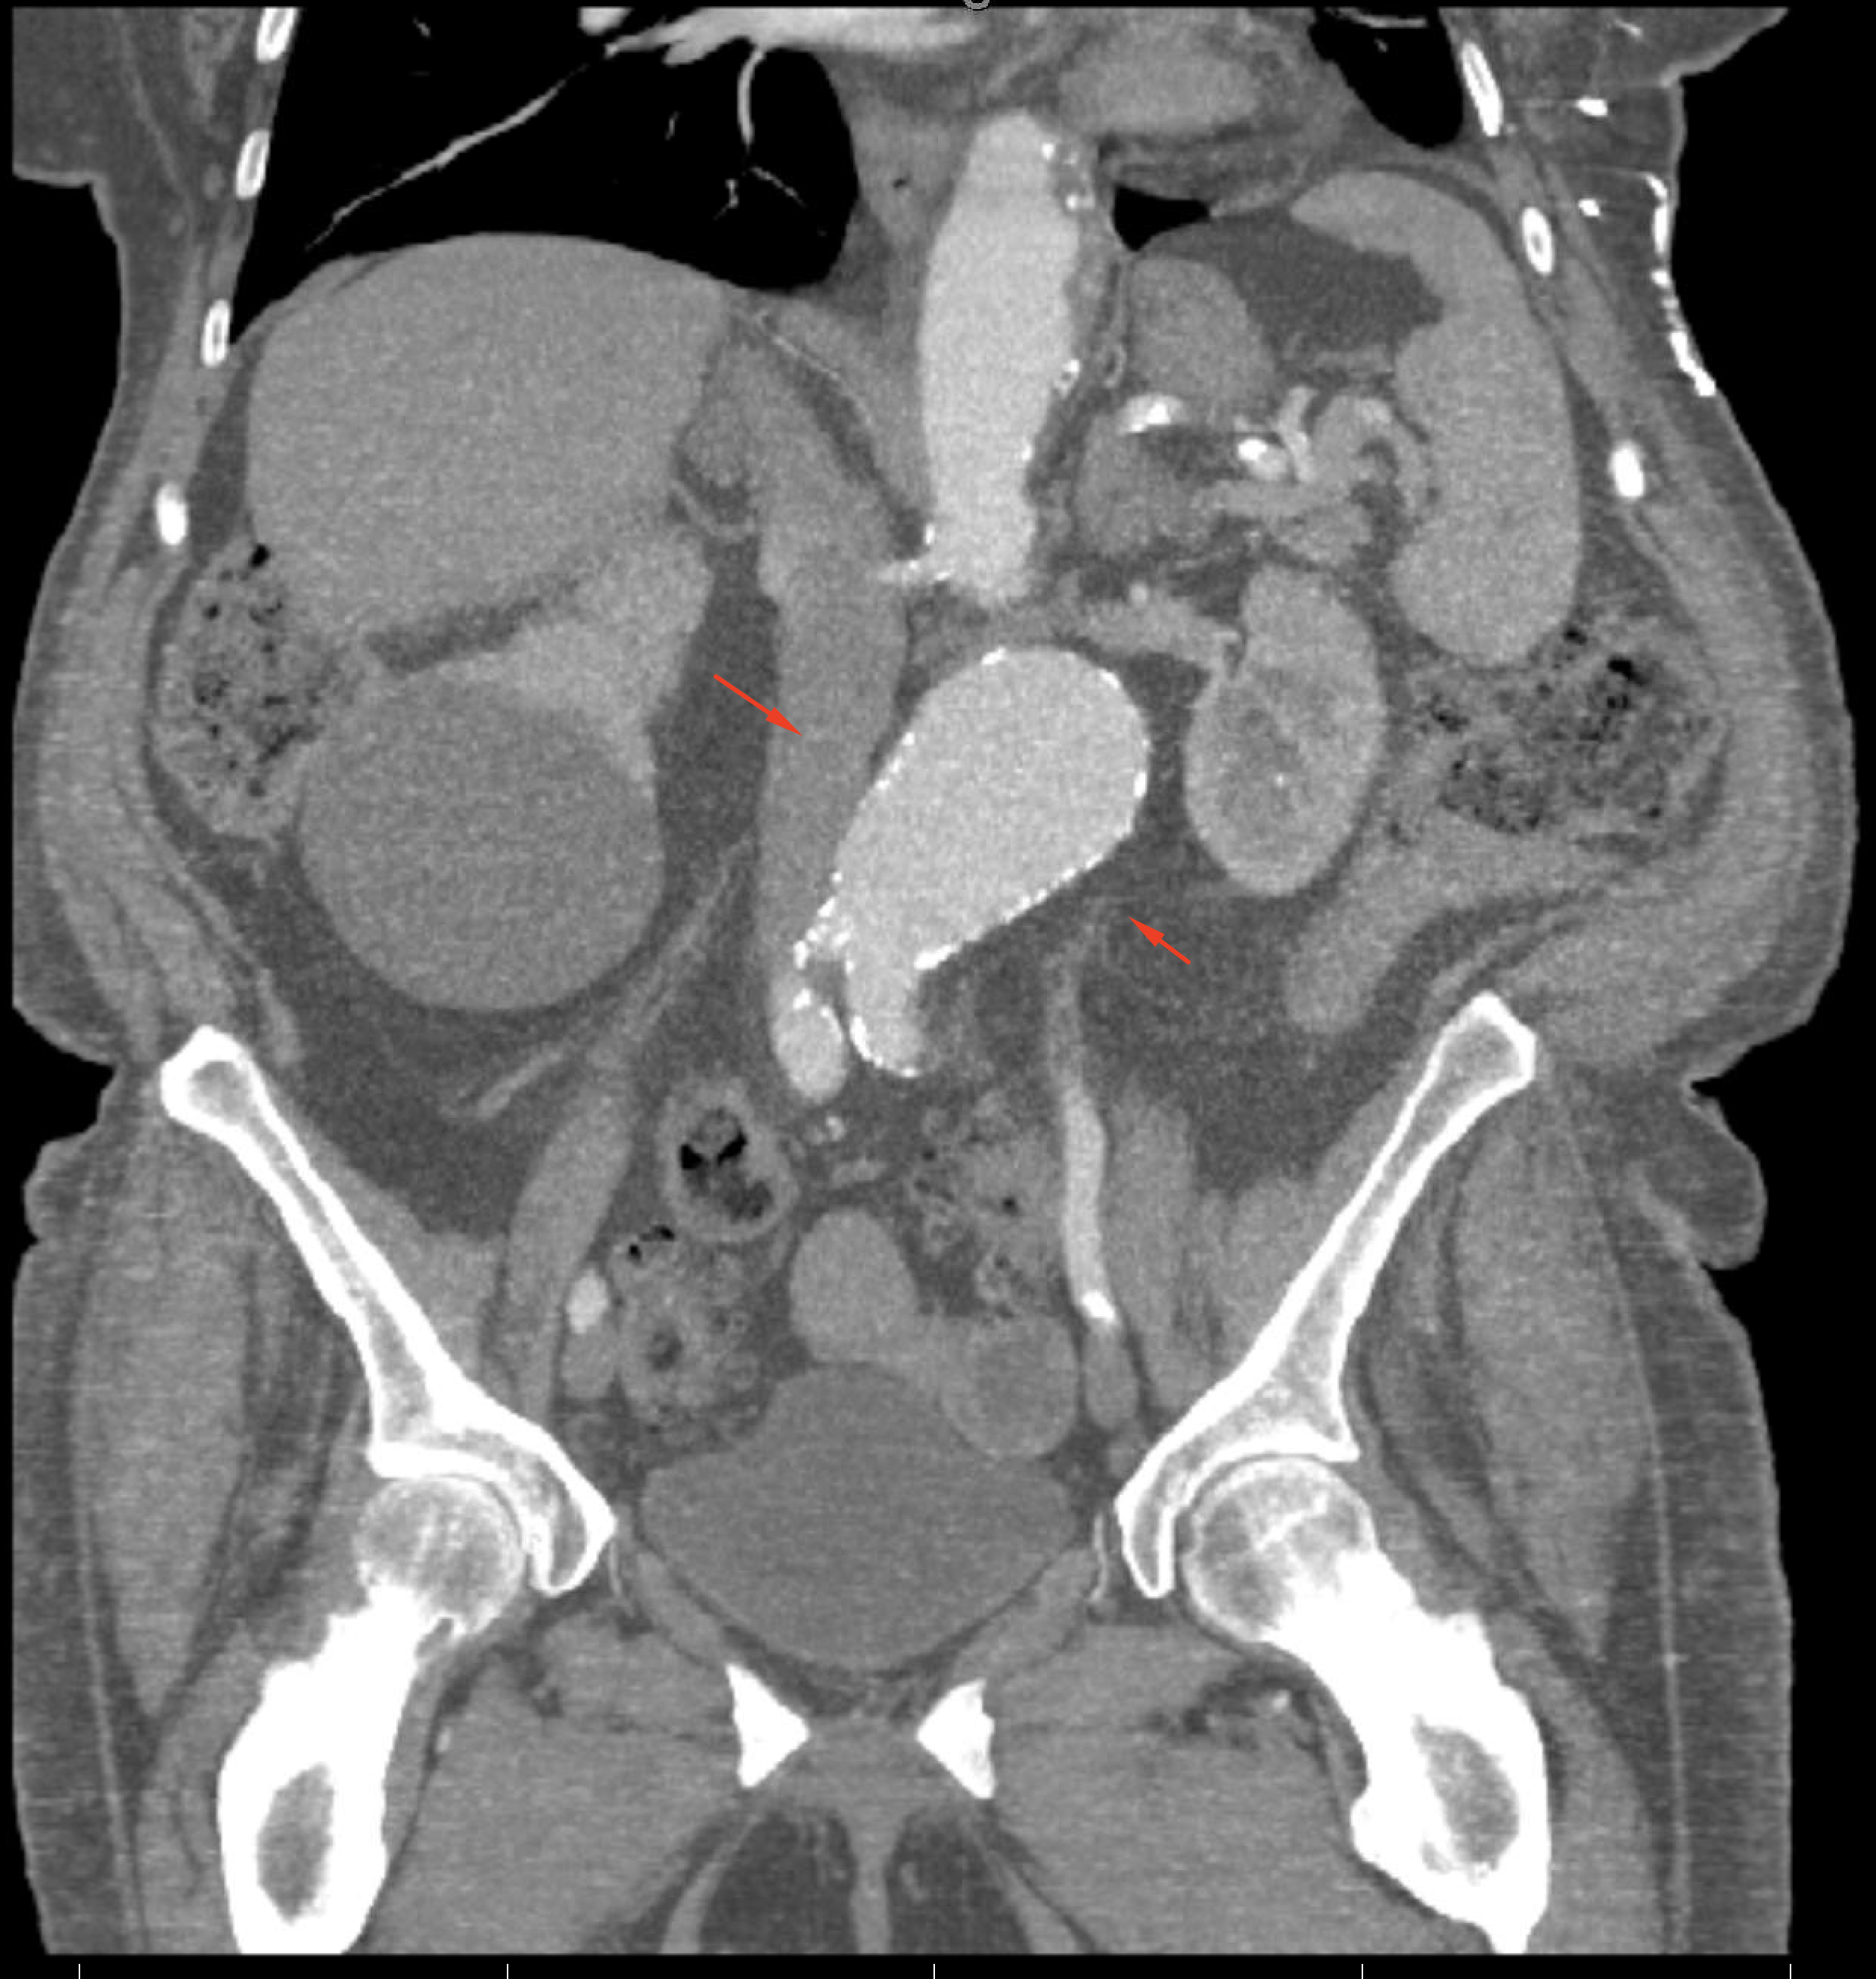

Age: 75

Sex: Female

Indication: Bright red blood per rectum, history of diverticulosis

Radiotracer: Tc99m labeled RBCs

Sample ReportNo evidence of active GI bleeding during the course of this exam.

Abdominal aortic aneurysm. Recommend CT or ultrasound for further assessment.